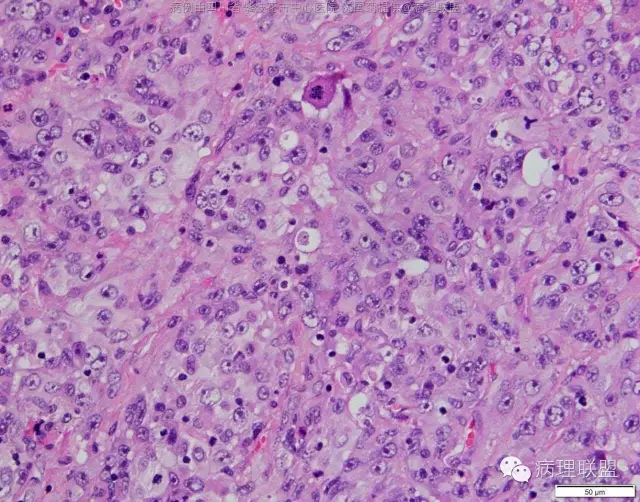

M/47 肺部占位( 肺大细胞癌?)

M/47 肺部占位,大小2*1*0.6cm(病例由四川攀枝花市中心医院 沈国菊提供,致谢!)

@张丽 免疫组化腺癌,鳞癌,神经内分泌,恶黑标记均为阴性,只有广谱CK跟Vimentin阳性,准备发大细胞癌

@沈国菊 肺大细胞癌的签发有时是个排他性诊断,我的体会:大细胞的标准:按淋巴细胞直径3倍来算,需要大于这个值,不能等于(从图给出,符合)。神经内分泌的标记(CD56 SYN CgA)完全阴性的可能性不是没有,建议重做试试;细胞的异型性大(符合);Ki67的指数高,应该非常高(您这里没有给出)。这仅仅是我个人体会,我说的不一定正确。

感谢您的精彩病例,采图非常漂亮,并且有标尺(特别赞)。魏老师,Ki-67阳性大于90%,送检7组淋巴结6/7见肿瘤转移。